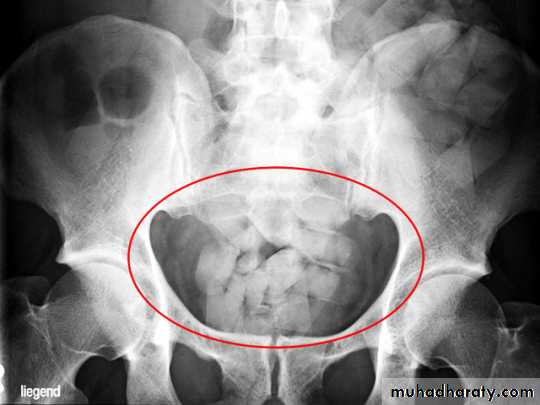

C-Radiographic examination:

-Limited role.-Lack of Radiopacity. (Undetectable by x ray).

-Plain X ray Of the Abdomen.

Foreign Body in GIT (Body packers)Latex plastic storage.